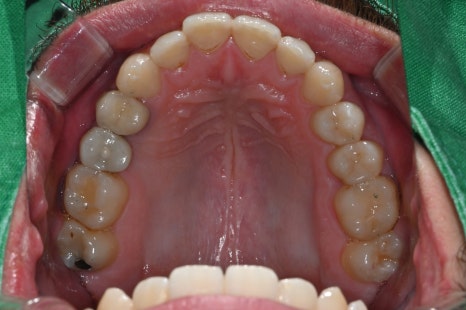

These are intraoral photos of the upper and lower teeth taken at the time of the visit.

Due to the loss of the second small molar on the upper right, implant treatment was needed.